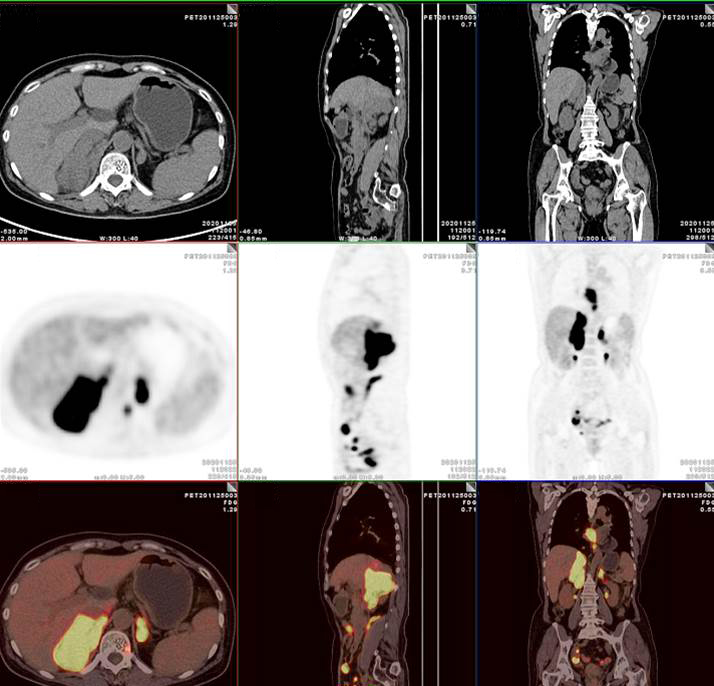

PET/CT影像圖

雙側(cè)腎上腺病灶、腹膜后淋巴結(jié)放射性攝取明顯增高

膽囊及雙腎上腺病灶、腹膜后淋巴結(jié)放射性攝取明顯增高

胃、雙腎上腺病灶、腹膜后淋巴結(jié)放射性攝取明顯增高